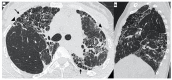

Background: Idiopathic pulmonary fibrosis (IPF) is a progressive fibrosing interstitial lung disease (ILD). This prospective observational study aimed at the evaluation of any correlation between genetic variants associated with IPF susceptibility and high-resolution computed tomography (HRCT) patterns. It also aimed at evidencing any differences in the HRTC pattern between the familial and sporadic form at diagnosis and after two years.

Methods: A total of 65 IPF patients (mean age at diagnosis 65 ± 10) were enrolled after having given written informed consent. HRCT and genetic evaluations were performed.

Results: A total of 19 familial (mean age 62 ± 15) and 46 sporadic (mean age 70 ± 9) IPF patients were enrolled. A statistically significant difference was evidenced in the HRTC pattern at diagnosis between the two groups. Sporadic IPF patients had a predominantly usual interstitial pneumonia (UIP) pattern compared with those patients with familial IPF (60.0% vs. 21.1%, respectively). Moreover, familial IPF patients had more alternative diagnoses than those with sporadic IPF (31.6% vs. 2.2%, respectively). Furthermore, there was a slight increase in the typical UIP pattern in the familial IPF group at two years from diagnosis.